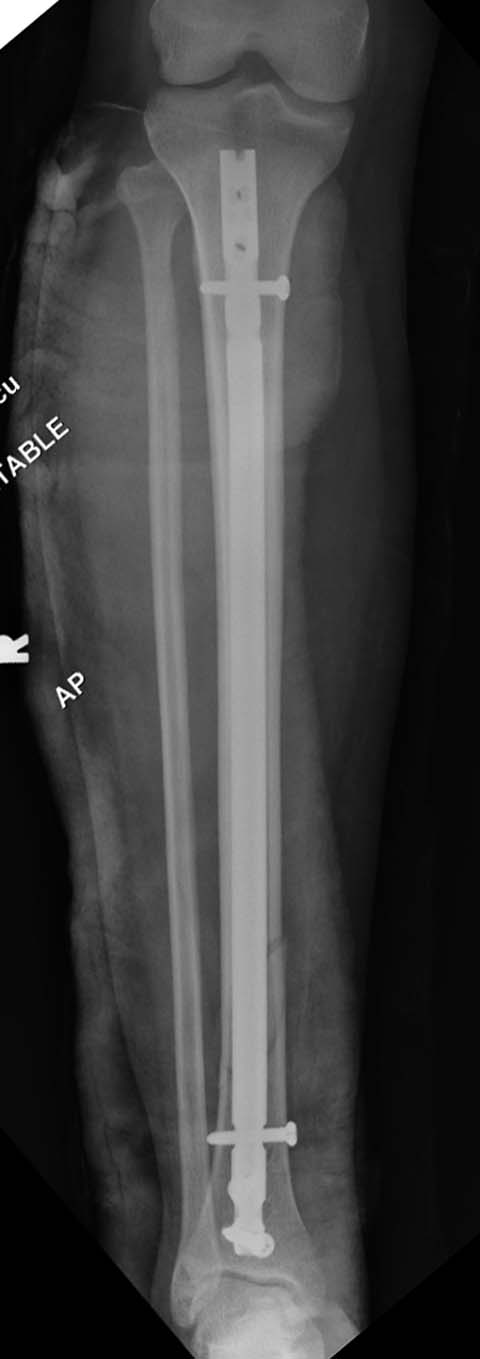

набора гвоздей повлияло на выбор короткого имплантата, имеется угловая и

ротационная деформации. Независимо от локализации, стабильность

создается, когда гвоздь проксимально не глубже 1.5 см (облегчает

удаление) и дистально доходит до epiphyseal scar.

Здесь несколько снимков изолированного перелома большеберцовой с

интактной малоберцовой.  Weber clamp, блокирующие спицы и риминг в

центре канала отрепонировал перелом....